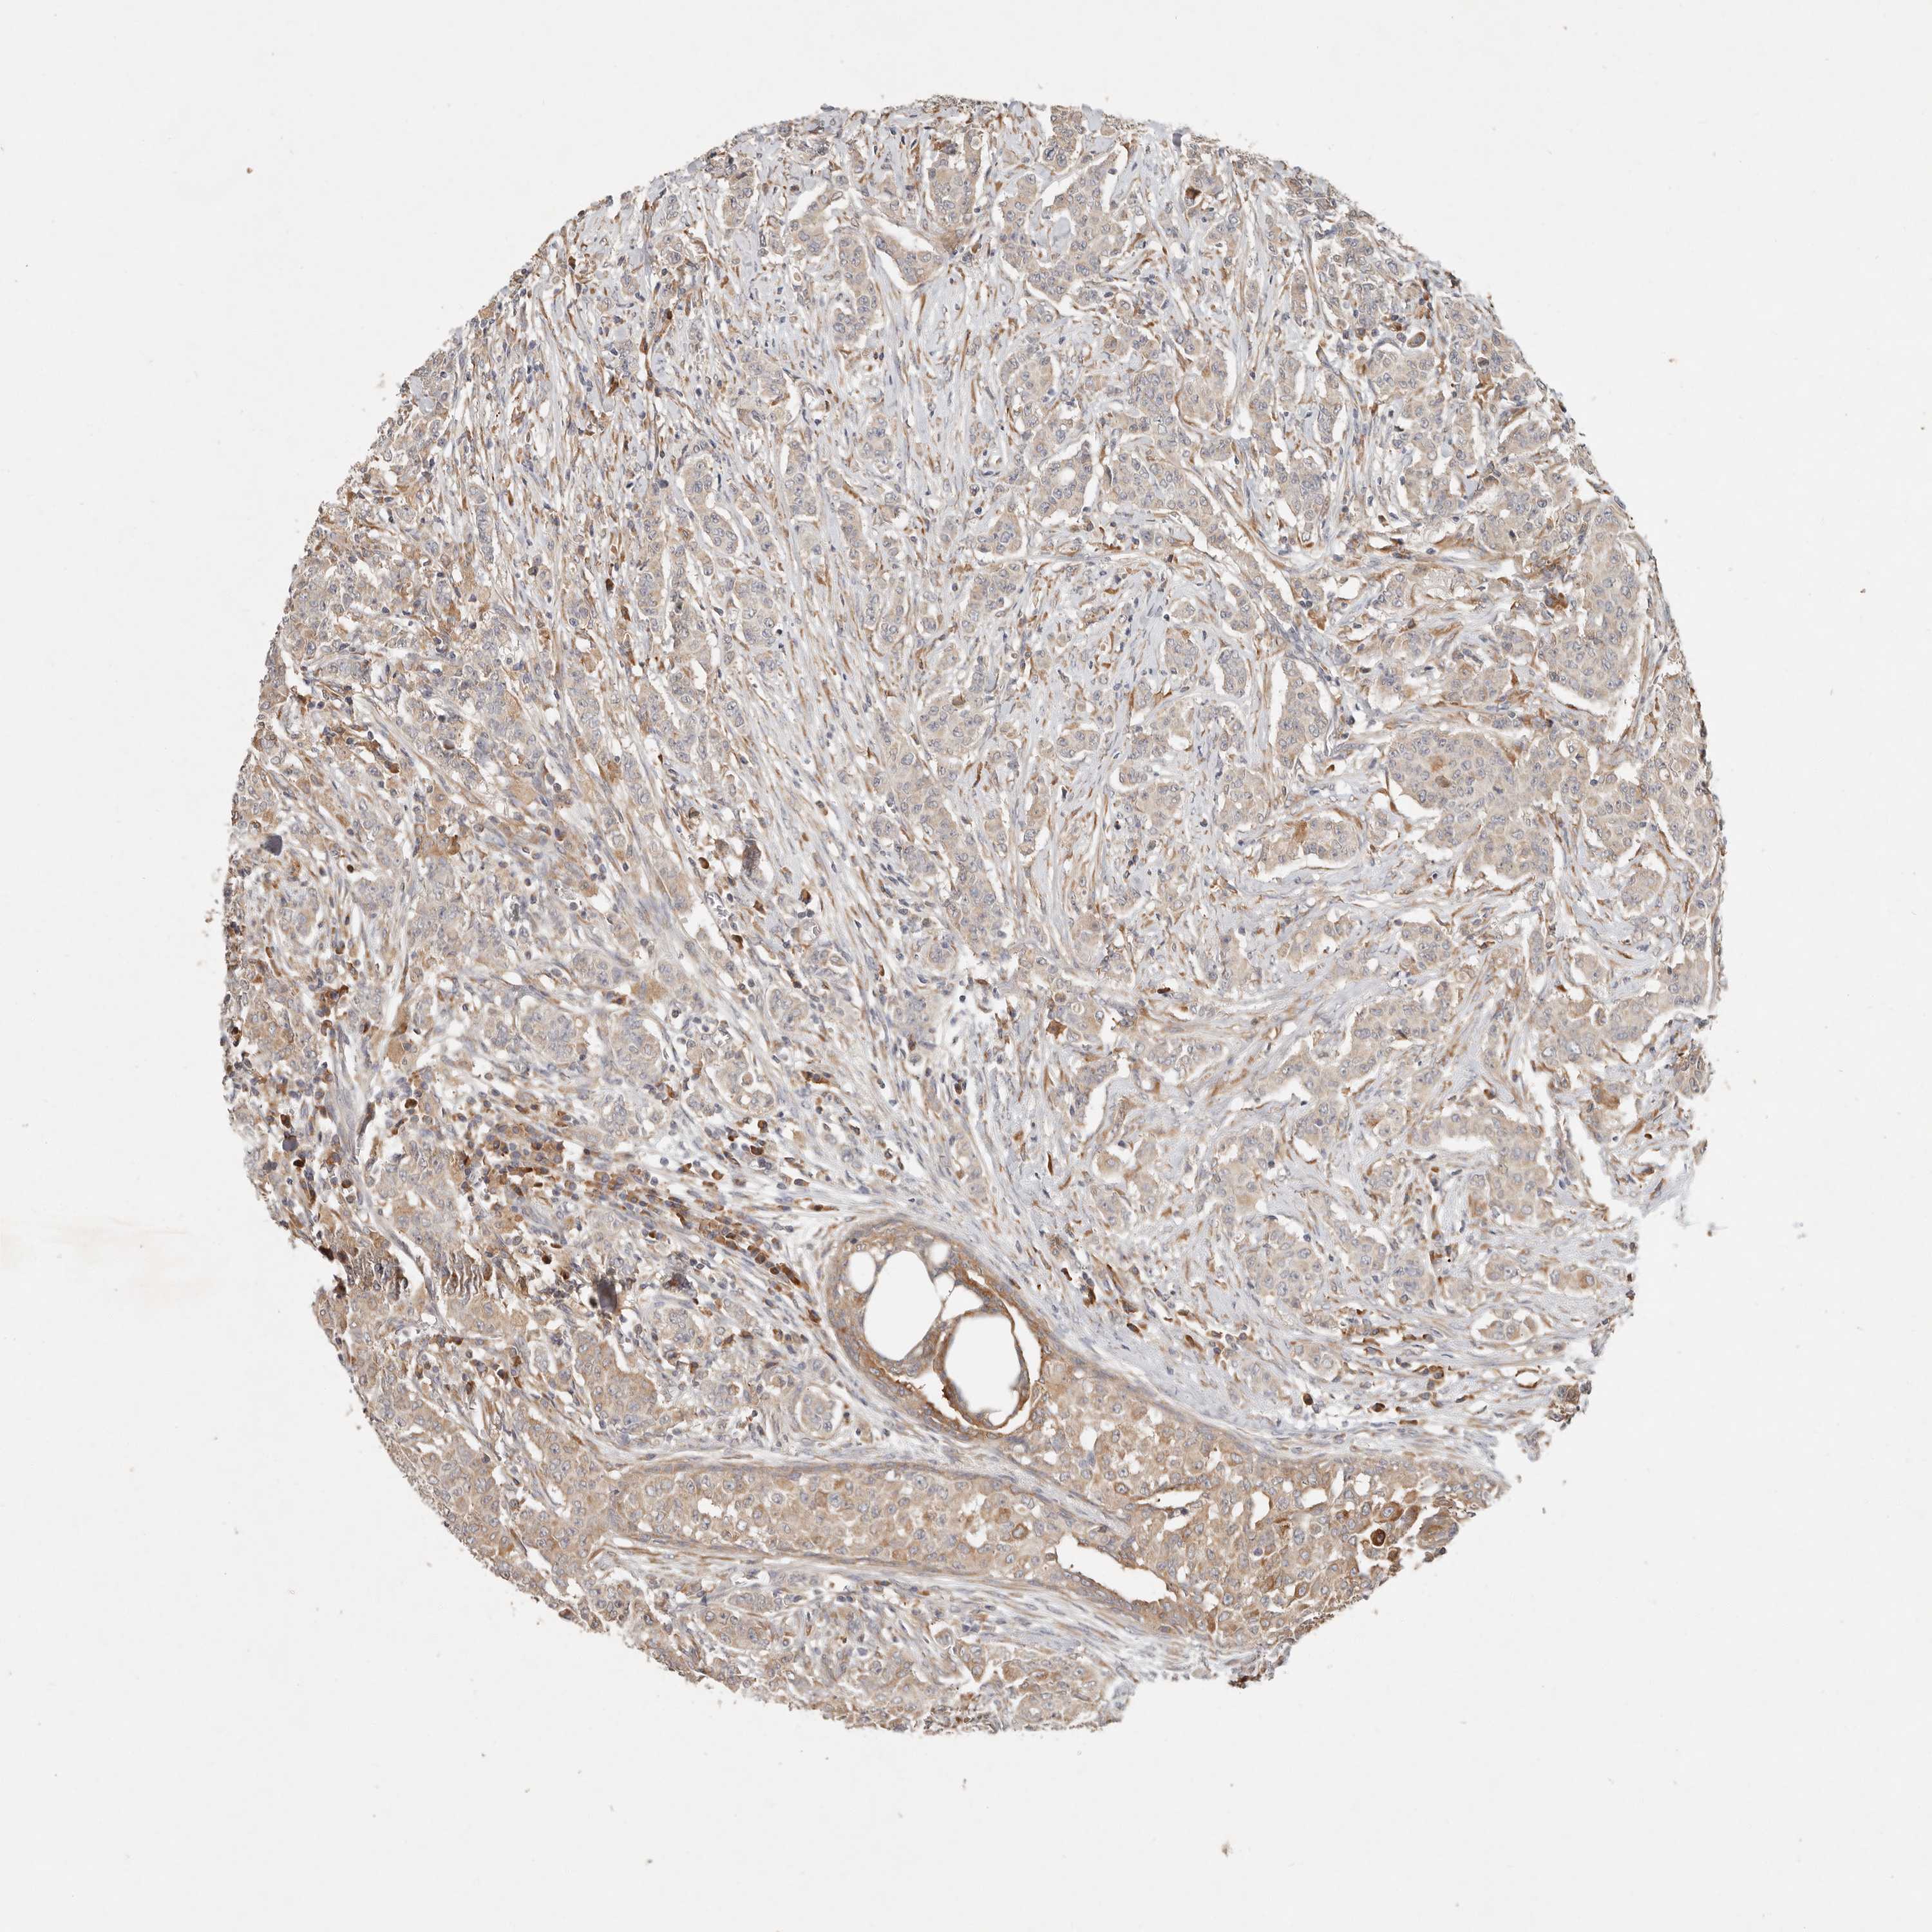

CANCER BREAST CANCER Show tissue menu

BRCA TCGA BRCA VALIDATION PROTEIN EXPRESSION